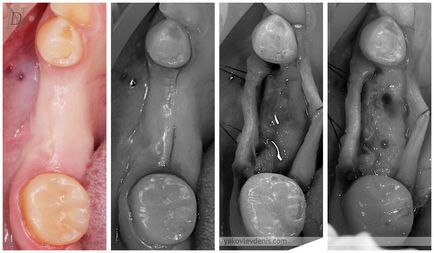

Beültetés kombinálható közvetlenül az eltávolítása a fog, ez csökkenti a tranzakciók száma és a kezelési időtartamot csökkenti. Ennek lényege abban rejlik, hogy a beültetés végezzük eltávolítás után azonnal. Az implantátumot ültetünk be a lyukba, ami képződik foghúzás után. Így nincs szükség arra, hogy további metszést. Sőt, gyakran a következő sebészeti beavatkozással és pánik betegek. Azaz, egy egyfokozatú beültetés kevésbé traumatikus, mint a klasszikus.

bizonyos típusú titán csavarok használhatók egyszintes implantáció, amelyek szerkezetileg eltérnek használják a klasszikus módon, ahogy jól kell rögzíteni a foghúzás lyuk.

Egy olyan helyzetben, amikor a front fogak eltávolítják, a beteg nem akarja, hogy a hiba az anterior és világos, hogy miért. Ilyen esetekben alkalmazzuk a módszer a közvetlen implantáció és fogpótlás ideiglenes koronát.

Ha az implantátum azonnal foghúzás után az ilyen problémák nem merülnek fel, mert a csont nem elsorvadt.

Ugyanakkor, azonnali implantáció közvetlenül a lyukba svezheudalennogo fogat többletinformációt hordoz kockázatokat.

Ha eltávolítja a fogat gyakran sérült csont esetében a telepítés ezen a helyen az implantátum növeli a szövődmények kockázata. Tipikusan egy orvos fogja tudni mondani, az biztos, talán hamarosan telepíteni az implantátum csak a foghúzás fog és értékeli a tényleges kár, hogy a csont. Ha azt tervezi, azonnali implantáció, a foghúzás fogó nem használ, és a speciális eszközök, nehogy traumás eltávolítását.

Ha az eltávolított fog körül megfigyelt gyulladás, sipoly, vagy periodontális betegség, azonnali implantáció nem alkalmazható.

Ebben a helyzetben van mestorezorbtsiya foggyökér, így azonnali implantáció módszer alkalmazható itt.